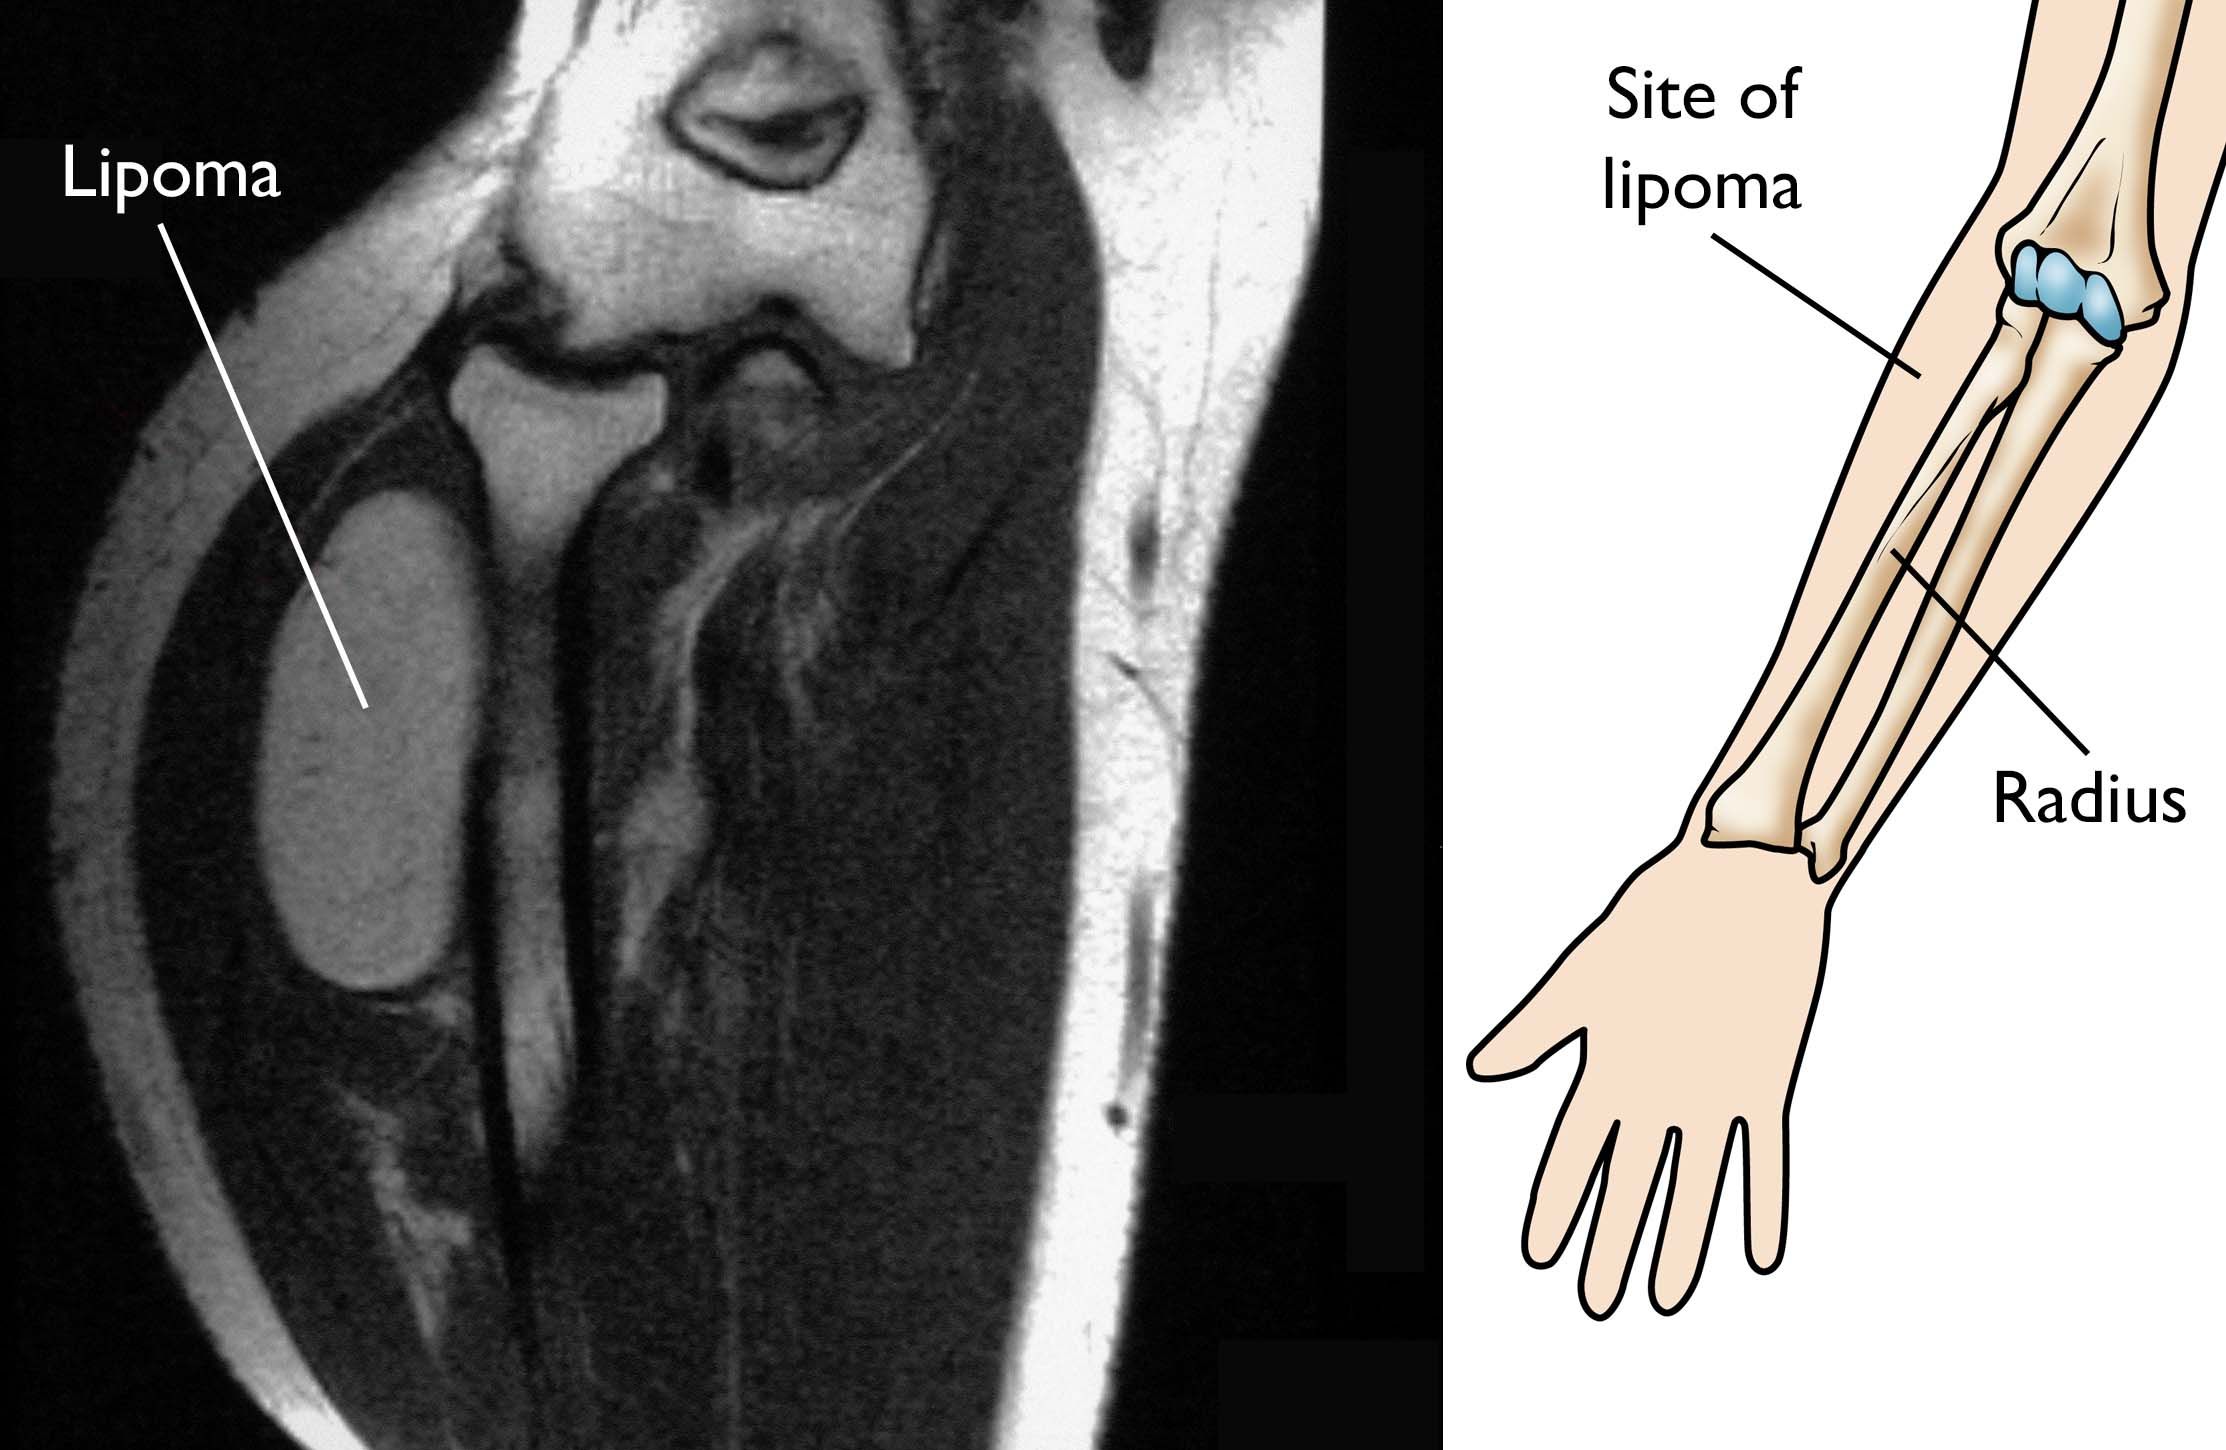

MRI of lipoma near elbow

(Left) An MRI scan of the elbow clearly shows the lipoma. (Right) The location of the lipoma in the adjacent MRI.